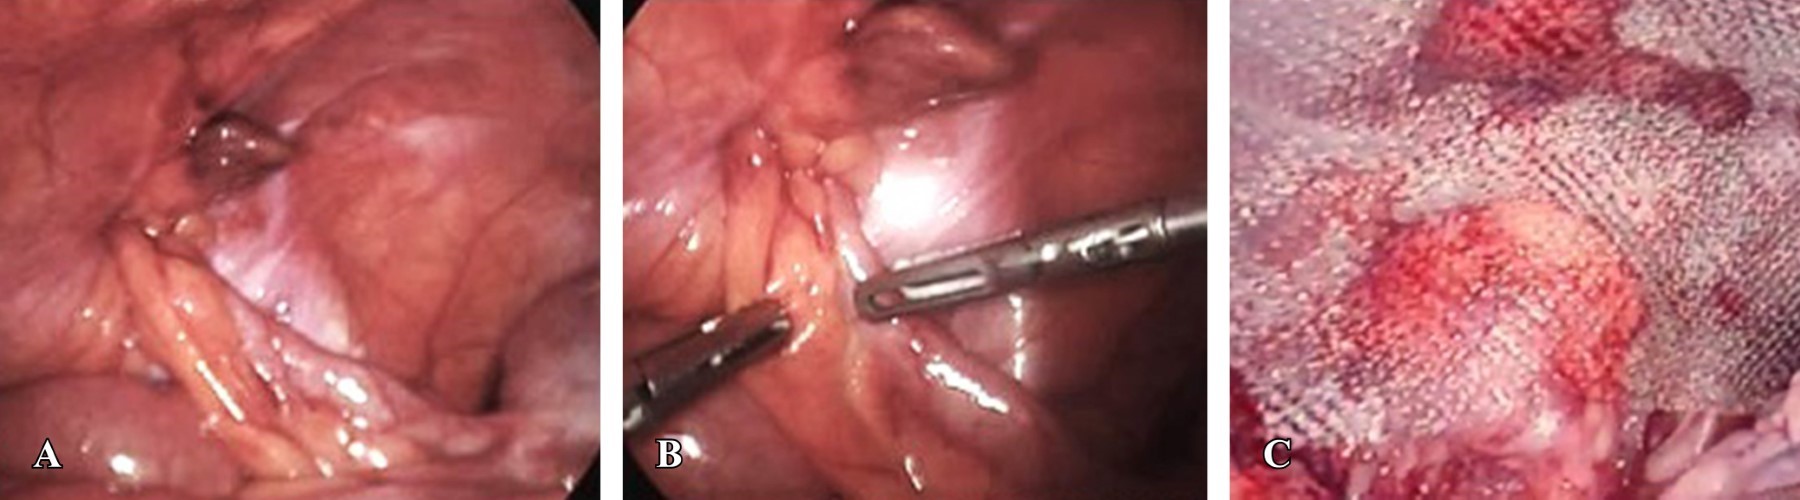

En uno de los pacientes se identificó una hernia de Amyand derecha con defecto indirecto cuyo saco contenía al apéndice cecal con diagnóstico de apendicitis no complicada. Se realizó plastia inguinal TAPP con colocación de malla de polipropileno de 12 × 10 cm, la cual se fijó con fijadores absorbibles a ligamento de Cooper, recto anterior y pared lateral del abdomen. Después se realizó cierre hermético del flap peritoneal con poliglactina 910. Una vez concluida la plastia inguinal, asegurando el cierre adecuado del peritoneo y cobertura completa de la malla, se realizó apendicectomía laparoscópica (Figura 5).

Al realizar la laparoscopía inicial, se encontró una hernia inguinal izquierda recidivante con contenido de borde antimesentérico del íleon (hernia de Richter) y fibrosis por malla previa. Se realizó reducción de saco herniario con evidencia de necrosis del segmento intestinal, sin datos de perforación. Se inició disección de flap peritoneal para continuar con plastia inguinal con técnica transabdominal preperitoneal con colocación de malla. Se colocó malla de polipropileno medianamente pesada de 15 × 12 cm. Se colocó malla con fijadores absorbibles a ligamento de Cooper, recto abdominal y pared lateral del abdomen. Se cerró peritoneo de forma hermética con surgete continuo con sutura barbada monofilamento de absorción lenta. Una vez terminada la plastia, se realizó ampliación del puerto umbilical para exponer el segmento intestinal comprometido de 7 cm. Se realizó resección intestinal con anastomosis laterolateral antiperistáltica mecánica con engrapadora lineal 75 mm. El cierre de las enterotomías se realizó de forma manual con puntos de Connel-Mayo. Se concluyó el procedimiento sin complicaciones asociadas (Figura 6).

Figura 5

Figura 6